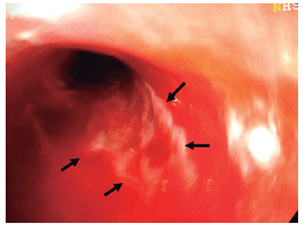

Mujer de 79 años, que consulta por urgencias por melanemesis y alteración de la conciencia. Como antecedente presentaba meningioma resecado, con síndrome convulsivo secundario, hipertensión arterial no controlada y enfermedad pulmonar obstructiva crónica. En los exámenes presentaba leucocitosis con neutrofilia (89 %); creatinina de 1,84 mg/dL, hipocloremia (92 mEq/L) e hiponatremia (129 mEq/L). La endoscopia mostró esfacelo del epitelio esofágico en los dos tercios inferiores y sangrado difuso en la capa (Figuras 1, 2, 3 y 4), sin cambios en el calibre. Se desconoce su evolución y su desenlace.

Los hallazgos endoscópicos son diversos y requieren que se descarten otras etiologías que producen alteraciones similares, como la ingestión de cáusticos, otros tóxicos o carbón, infecciones, radioterapia o melanoma metastásico, entre otros 3,10. Los hallazgos pueden ir desde membranas blanquecinas, que al removerlas dejan una mucosa grisácea o negruzca, hasta necrosis difusa con exudados amarillentos adherentes, ulceración en la mayoría y aspecto negruzco o grisáceo, demarcado por la unión gastroesofágica, con región cardial de aspecto usual, como se describen en nuestros casos. El espectro de lesiones asociadas es amplio, como hemorragia gástrica o duodenal, ulceraciones y perforaciones, representadas en la casuística general con úlceras duodenales (10; 4 %), gástricas (2; 1 %), necrosis isquémica duodenal (2; 1%); sangrado activo (4; 2 %), perforación esofágica (3; 1,3 %) y duodenal (1; 0,5 %) (Tabla 1).